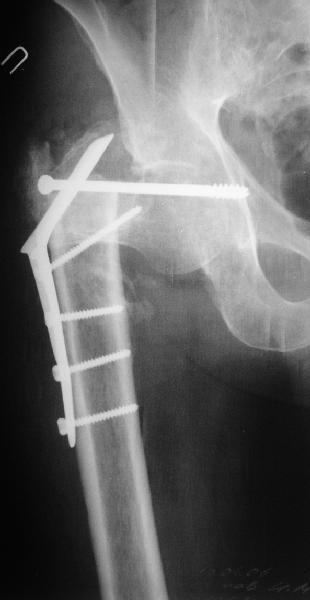

В приложении пример пациента, близкого по картине к тому, что представил Виктор (варус и смещение периферического отломка на поперечник кзади). Сделали как раз то, что Виктор исходно намеревался - аппаратная коррекция и затем гамма.